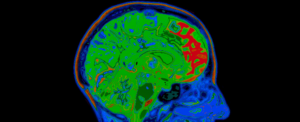

Вони використовували функціональну магнітно-резонансну томографію (ФМРТ) для аналізу мозкової активності та однофотонну емісійну комп’ютерну томографію (ОФЕКТ) для вимірювання рівня дофаміну через 30 хвилин після введення поживних речовин.

У худорлявих учасників знижувалася активність мозку в різних ділянках після вливання глюкози і жиру. Після введення поживних речовин активність у смугастому тілі знижувалася, а рівень дофаміну підвищувався.

Але мозкова активність людей з категорії ожиріння не змінилася. Їхній стриатум залишався активним, і після вливання жирів дофамін, який пов’язаний з функцією стриатуму, не вивільнявся в значних кількостях.

Вивільнення дофаміну спостерігалося у відповідь на глюкозу в обох групах, хоча у людей з ожирінням воно суттєво не впливало на мозкову активність, а на жир – лише у худих учасників.